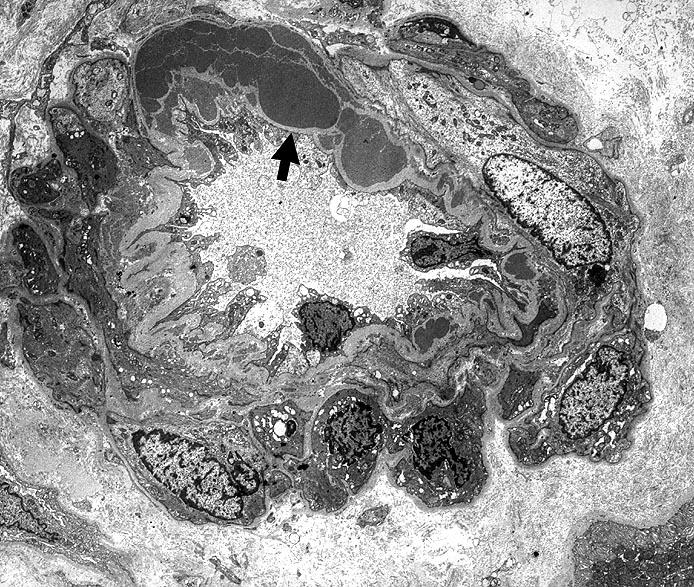

PathoPic – image database / PathoPic ID 1913 - Arteriolosklerose bei Diabetes Frühstadium

Arteriolosklerose bei Diabetes Frühstadium

Innerhalb der Basalmembran gelegene plumpe Proteinablagerungen. Die glatten Muskelzellen sind in der gesamten Peripherie erhalten.

Typisch für Diabetes mellitus ist der Befall von Vas afferens und efferens, oft auch der Vasa recta. In intrarenalen Arterien unspezifische Atherosklerose teilweise mit Atheromen (typisch für Diabetes). Der Schweregrad korreliert im allgemeinen mit dem Ausmass der exsudativen Läsionen der Glomerulosklerose. Die Arteriolosklerose im Vas afferens beim Diabetes ist identisch mit der Arteriolosklerose bei arterieller Hypertonie.